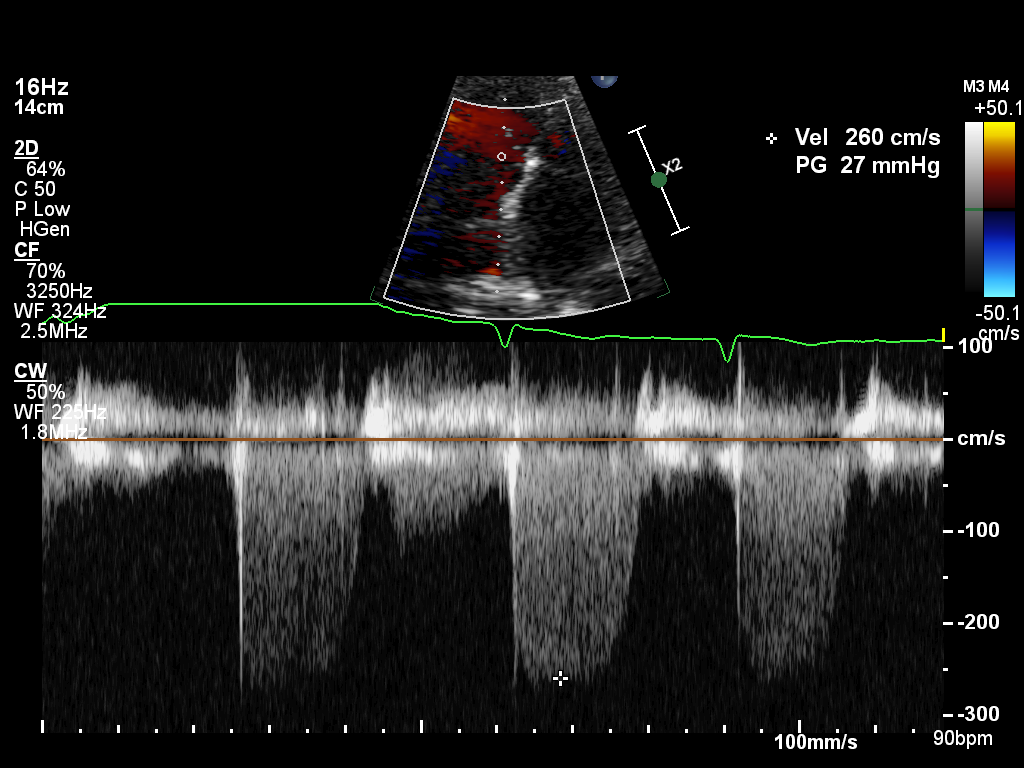

doppler-ao doppler-ao Spectral Doppler of the descending aorta

doppler-av doppler-av Spectral Doppler of the aortic valve

doppler-mv doppler-mv Spectral Doppler of the mitral valve

doppler-pv doppler-pv Spectral Doppler of the pulmonary valve

doppler-tissue-lateral doppler-tissue-lateral Tissue Doppler of the LV lateral wall

doppler-tissue-rv doppler-tissue-rv Tissue Doppler of the RV free wall

doppler-tissue-septal doppler-tissue-septal Tissue Doppler of the LV septal wall

doppler-tv doppler-tv Spectral Doppler of the tricuspid valve